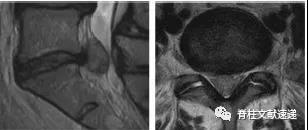

图注:椎间盘囊肿

图注:23岁男性,椎间盘囊肿。术中见波动的椎间盘囊肿并切除。